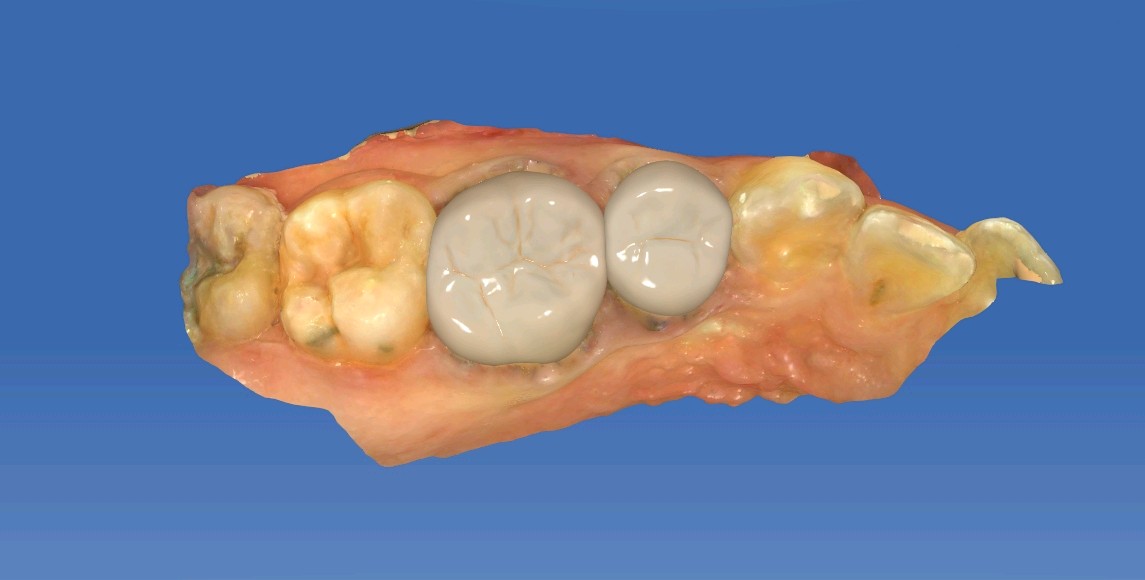

术中